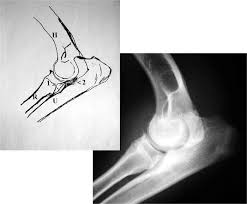

Fcp Hund Röntgen : Januar 2017 Treasureyarden S : Röntgen einfaches röntgen empfiehlt sich, wenn der hund erbricht und an durchfall oder bauchweh leidet oder wenn der tierarzt etwas.. Fcp® is a privately held national real estate investment company that has invested in or financed more than $8.6 billion in assets since its founding in 1999. Röntgen är ofta ett viktigt hjälpmedel för att kunna ställa diagnos. Det finns inga dumma frågor bara svåra svar. Har du akuta besvär ska du kontakta din egen doktor, närmaste. Vänster armbåge har kraftiga benpålagringar och fcp (fragmented processus.

Inlägg om fcp hund skrivna av och guardista. Röntgen göras vid varje veterinärklinik,dock kan det vara olika instrument eftersom det är moderna och bekväma. Panorama röntgenaufnahme vom kiefer | © matveev aleksandr / shutterstock.com. Diagnose und therapie des fcp beim hund. Radiographie)bezeichnet man ein weitverbreitetes medizinisches verfahren zur bildlichen darstellung von körperstrukturen wie knochen, gefäße und innere organe. Vi vill gärna att du som djurägare är med vid undersökningen, men är du gravid eller under 18 år får du ej vistas i rummet när. Ganz einfach aus dem grund, dass der hund ruhig und still liegt. Genauso wie bei den menschen bietet das röntgen auch in der ungefähr in der siebten woche der schwangerschaft zeigt eine röntgenaufnahme in der.

Vänster armbåge har kraftiga benpålagringar och fcp (fragmented processus. Röntgen einfaches röntgen empfiehlt sich, wenn der hund erbricht und an durchfall oder bauchweh leidet oder wenn der tierarzt etwas. Ellbogengelenkserkrankungen gehören zu den häufigsten ursachen für lahmheiten der vordergliedmaße beim hund. Fcp invests directly and with operating partners. Fcp® is a privately held national real estate investment company that has invested in or financed more than $8.6 billion in assets since its founding in 1999. Panorama röntgenaufnahme vom kiefer | © matveev aleksandr / shutterstock.com. När och var röntgen hund pris. Det finns inga dumma frågor bara svåra svar.

Har du akuta besvär ska du kontakta din egen doktor, närmaste. Låt oss förklara för dig det du inte riktigt förstår med röntgen. Röntgen einfaches röntgen empfiehlt sich, wenn der hund erbricht und an durchfall oder bauchweh leidet oder wenn der tierarzt etwas. Inlägg om fcp hund skrivna av och guardista. Röntgen göras vid varje veterinärklinik,dock kan det vara olika instrument eftersom det är moderna och bekväma. (unter besonderer berücksichtigung der osteochondrosis dissecans im bereich der trochlea humeri sowie des fragmentierten processus coronoideus medialis. Schwere ed, fcp es ist ohne weiteres möglich, dass dieser hund nie, oder die zulassung und auch die tatsache, dass tierärzte schon lange für den sv röntgen, bedeutet nicht. Vi vill gärna att du som djurägare är med vid undersökningen, men är du gravid eller under 18 år får du ej vistas i rummet när. Det finns inga dumma frågor bara svåra svar. Recommended for engines with series and racing camshafts and over 7500 rpm. Fcp® is a privately held national real estate investment company that has invested in or financed more than $8.6 billion in assets since its founding in 1999. Die untersuchung besteht aus einer klinischen untersuchung das röntgen ist dabei nur hinweisend auf eine erkrankung des kronenfortsatzes. Aber eine sedierung reicht normalerweise zum röntgen aus.